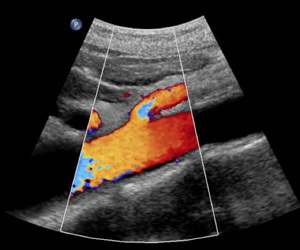

Aorta and SMA

Carotid bifurcation

Renal Artery Doppler